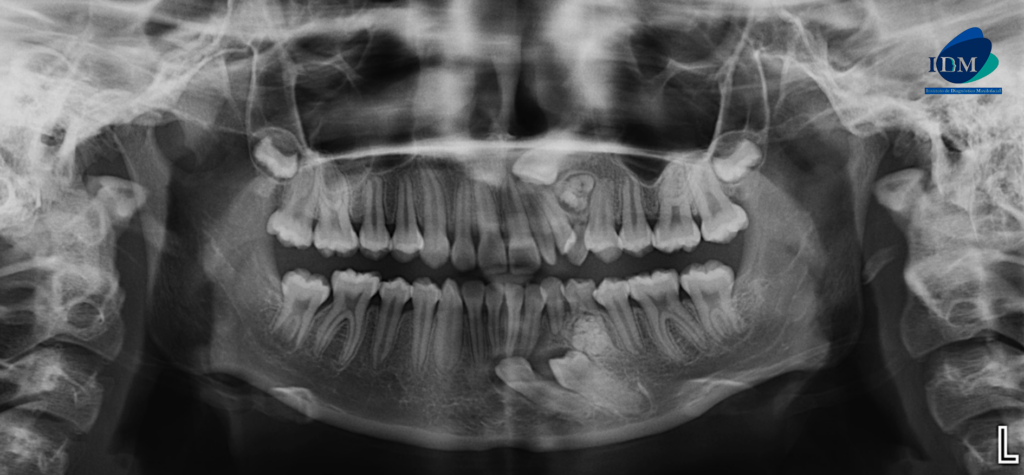

En la radiografía panorámica (Figura 1), se aprecia mineralización parcial del proceso estilohiodeo izquierdo, neumatización alveolar de senos maxilares, imagen radiopaca circunscrita de un halo radiolúcido proyectada entre los segmentos radiculares de piezas 22 – 24 y tercio medio radicular de pieza 74.

Radiografia Panorámica